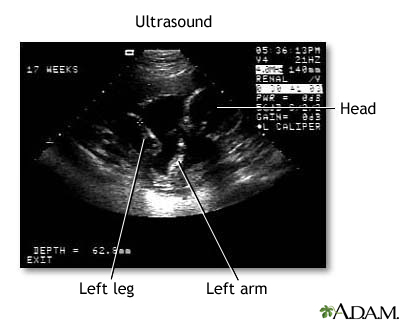

Ultrasound uses high-frequency sound waves to make images of organs and structures inside the body.

An ultrasound machine makes images so that organs inside the body can be examined. The machine sends out high-frequency sound waves, which reflect off body structures. A computer receives the waves and uses them to create a picture. Unlike with an x-ray or CT scan, this test does not use ionizing radiation.

- Pregnancy

Results are considered normal if the organs and structures being examined look OK.